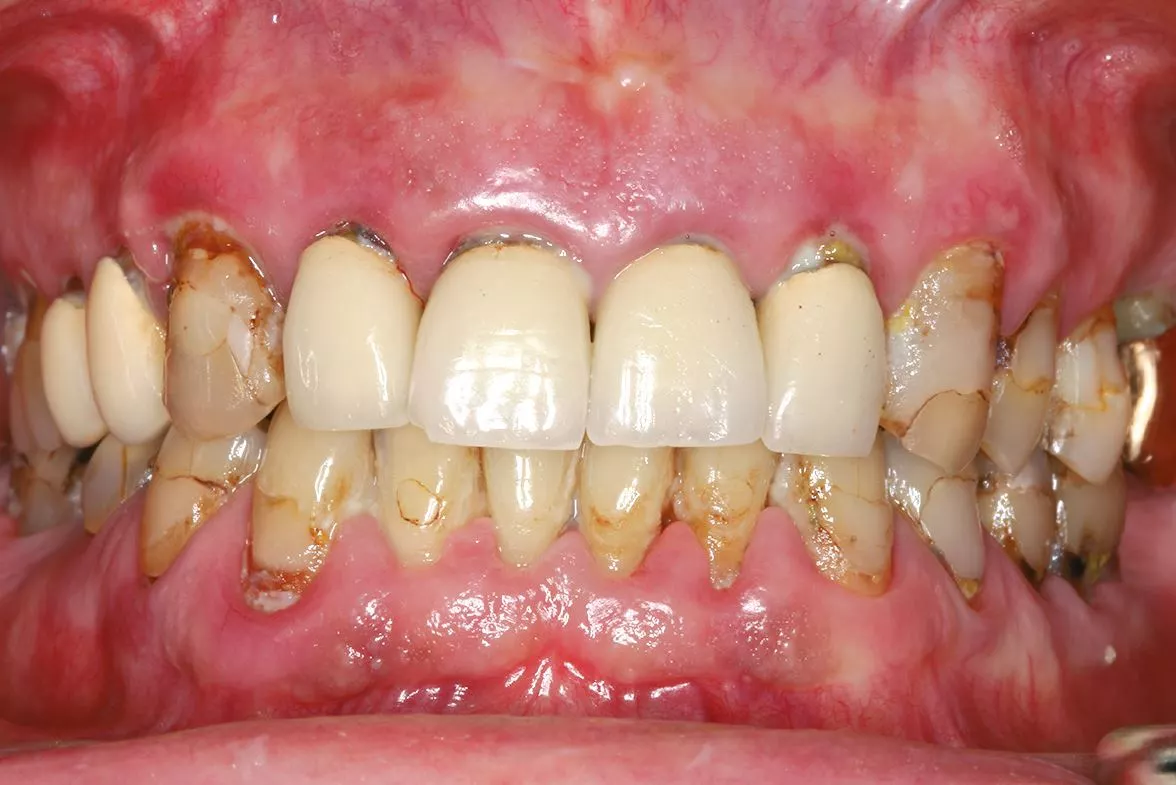

Daher haben sich in der Vergangenheit zum Beispiel Zentren für die Durchführung der Implantatplanung etabliert [6]. Für die prothetisch orientierte Planung benötigt das Planungszentrum neben den Informationen über die gewünschte Position und Anzahl der Implantate und die Unterlagen über das Knochenangebot, die anatomische Struktur und die Bißlage. Diese Daten können über konventionelle Abdrücke oder intraorale Scans der Kiefer, sowie mittels dreidimensionaler Röntgenaufnahmen zur Verfügung gestellt werden (Abb. 1-3). Mit diesen Unterlagen kann dann die Implantatplanung mit Umsetzung einer Navigationsschablone sowie die Herstellung eines Provisoriums erfolgen [4].

In einem nächsten Schritt kann man dann eine geführte Einzelzahnsofortversorgung durchführen. Der gezeigte Fall stellt den Abschluss einer solchen Entwicklung dar. Die Plattform erleichtert dem Anwender auch komplexe Versorgungen mit vertretbarem Aufwand sicher und mit einem geringen Komplikationsrisiko zu erreichen (Abb. 13-14). Nach einer Einarbeitung mit dem digitalen Workflow, können dann wieder je nach Investitionsvolumen Arbeitsschritte in der eigenen Praxisstruktur etabliert werden, um den Leistungsumfang wieder stärker in der praxiseigenen Prozesskette einzubinden.